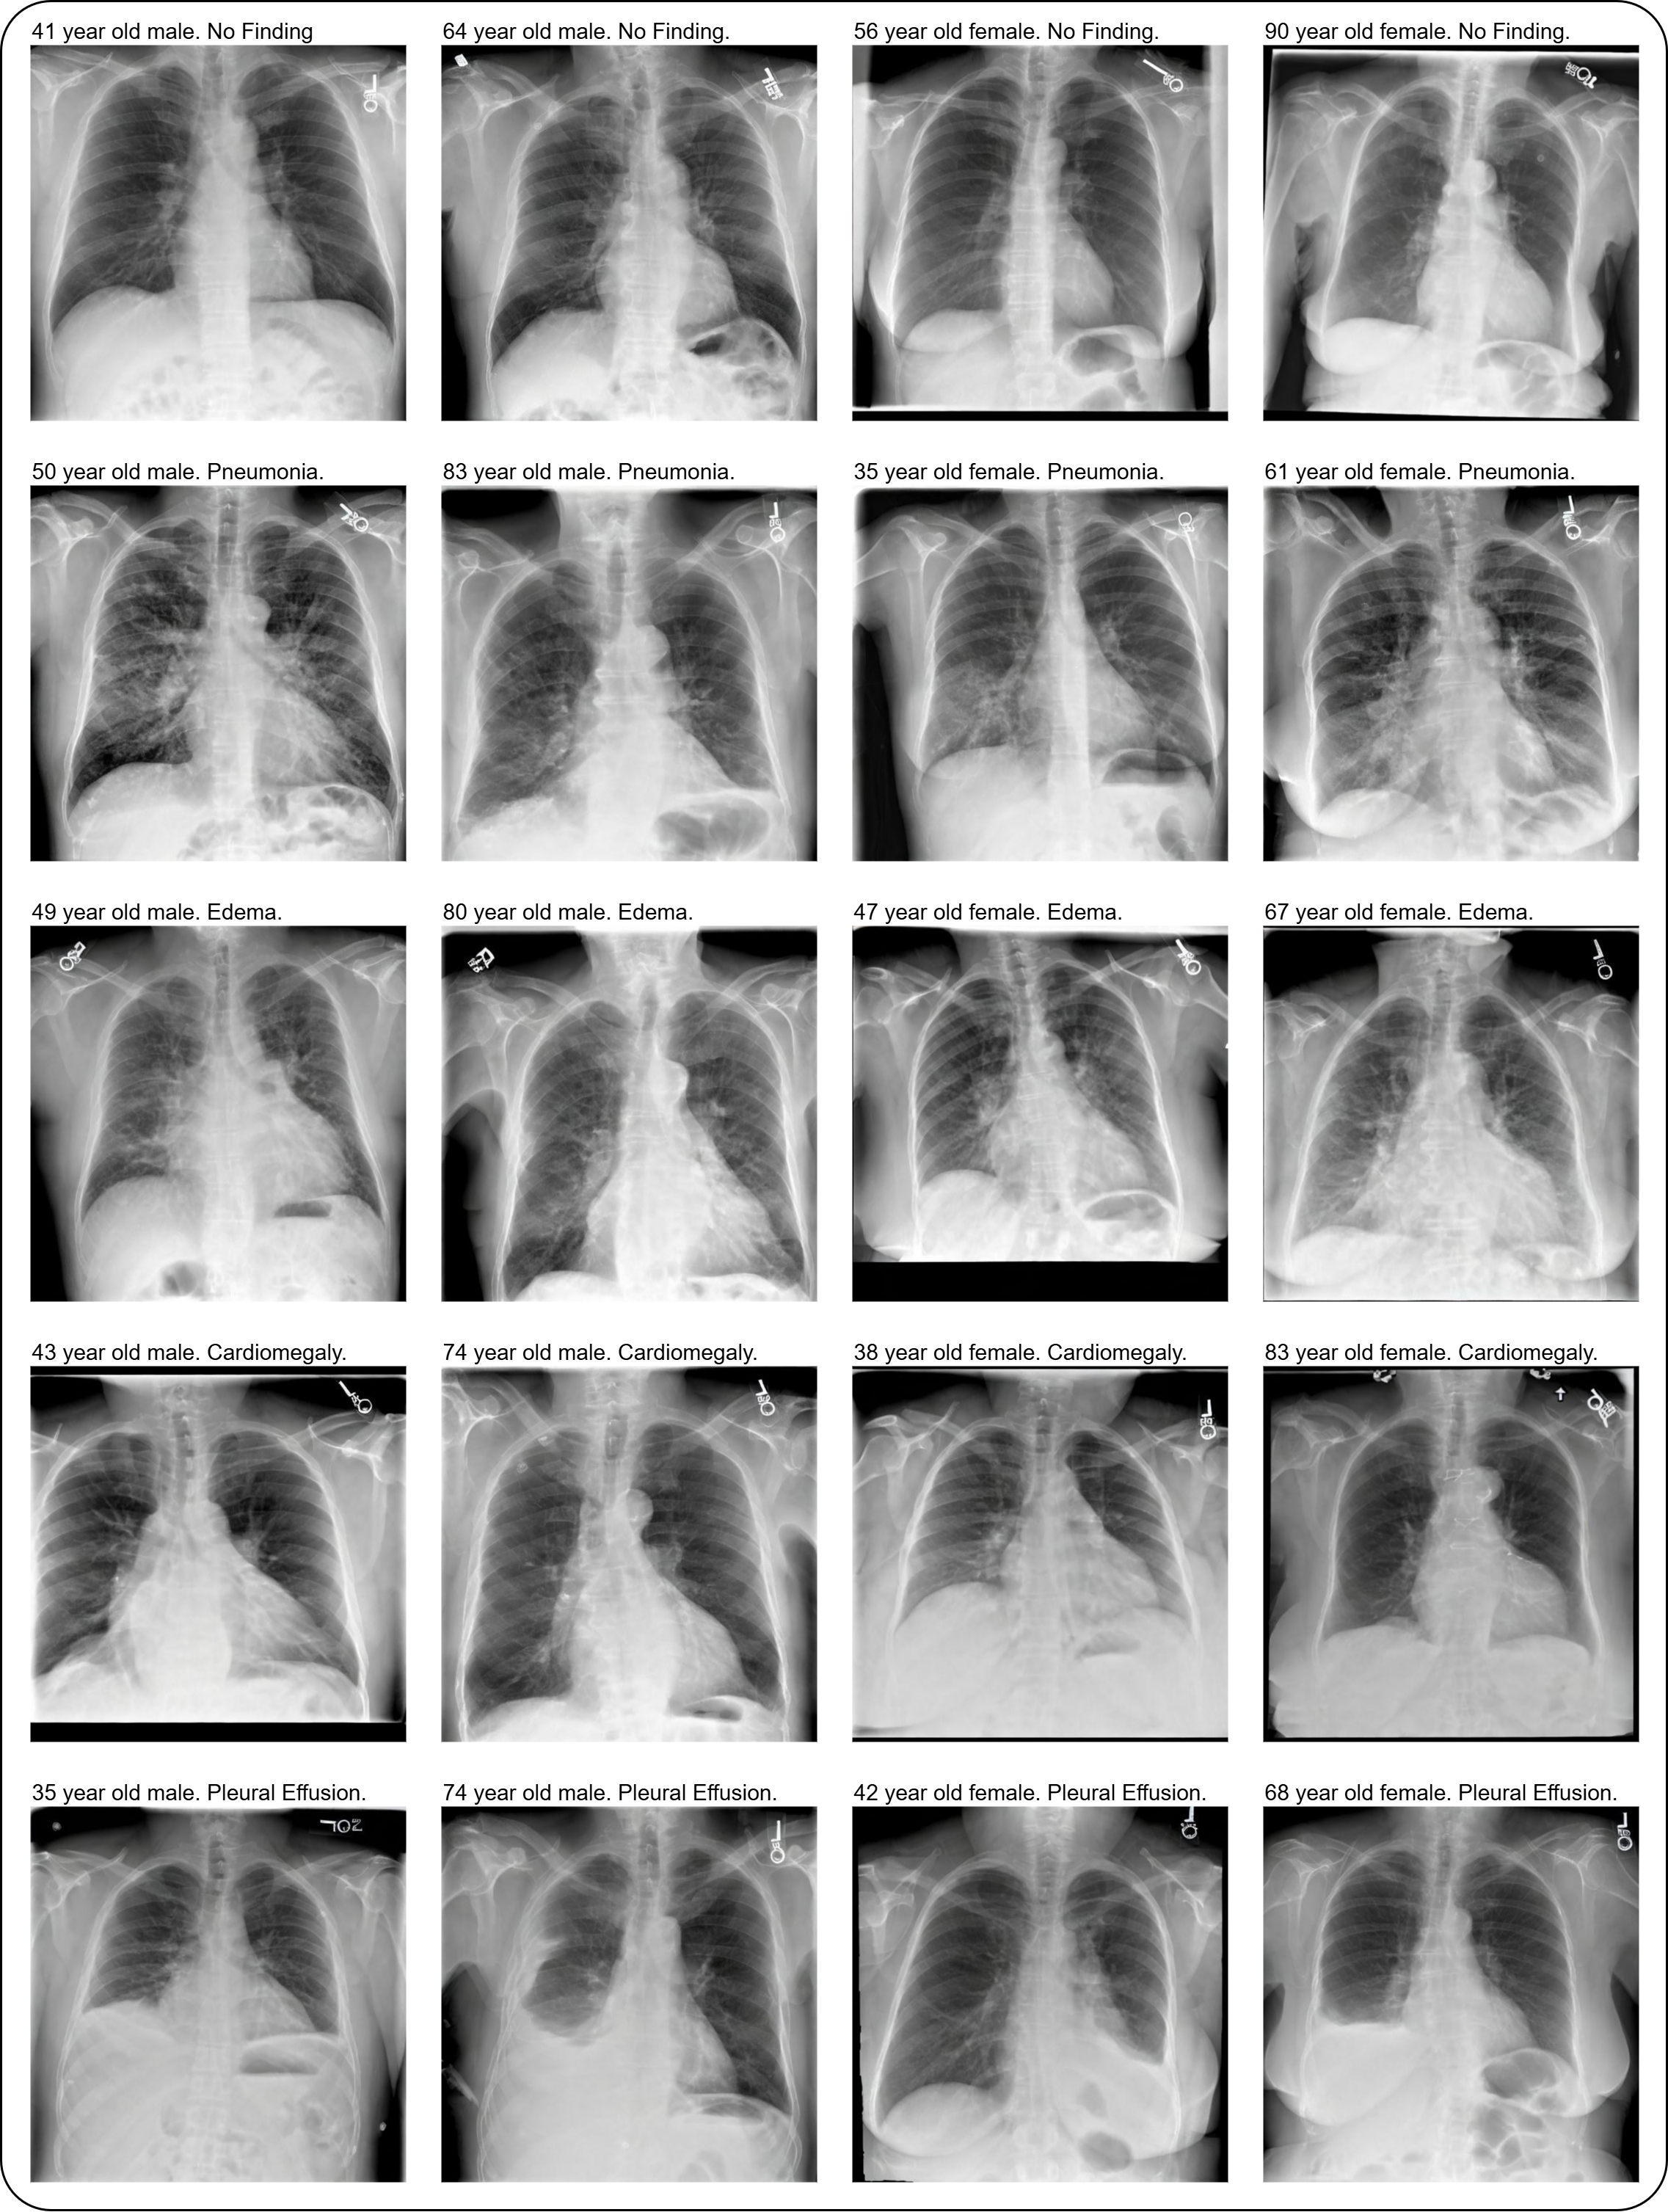

🩻 Synthetic CXR Dataset

565k synthetic chest radiographs and associated text prompts: stanfordmimi/RoentGen-v2-synthetic-dataset

Important: The generated images are for research and educational purposes only and cannot replace real chest x-rays for medical diagnosis.

title={Improving Performance, Robustness, and Fairness of Radiographic AI Models with Finely-Controllable Synthetic Data},